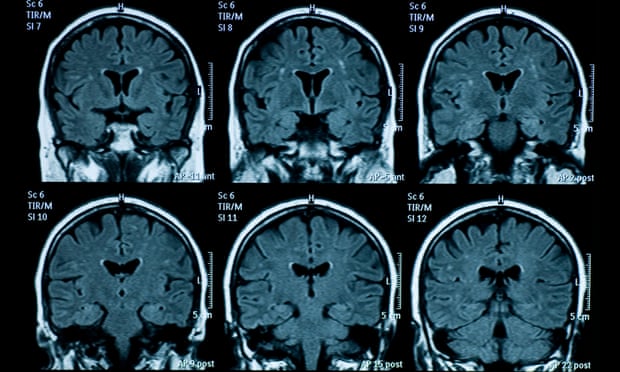

Não của thanh thiếu niên có dấu hiệu lão hóa nhanh hơn sau đại dịch COVID-19. Kết quả nghiên cứu mới đây đã phát hiện ra rằng bộ não của những thanh thiếu niên trải qua đại dịch COVID-19 có dấu hiệu lão hóa sớm hơn.

Theo trang The Guardian (Anh), các nhà nghiên cứu đã chụp ảnh cộng hưởng từ (MRI) của 81 thanh thiếu niên ở Mỹ trước đại dịch (từ tháng 11/2016 đến tháng 11/2019), và so sánh với ảnh chụp MRI của 82 thanh thiếu niên trong thời gian đại dịch bùng phát, nhưng là sau khi dỡ bỏ lệnh phong toả (dữ liệu được thu thập từ tháng 10/2020 đến tháng 3/2022).

Cụ thể, so với trước đại dịch, nhóm thanh thiếu niên ở giai đoạn hậu phong tỏa có vỏ não mỏng đi và sự phát triển của vùng hồi hải mã và hạch hạnh nhân lớn hơn. Điều này cho thấy các quá trình phát triển não đã tăng tốc. Nói cách khác, bộ não của họ đã già đi nhanh hơn.

Sự khác biệt về tuổi của não bộ là khoảng 3 năm. Ảnh: Getty Images